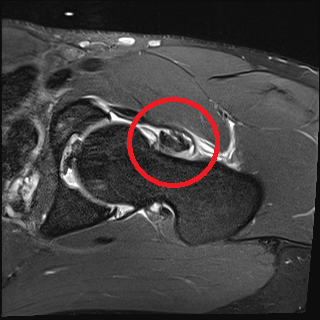

MRT-Aufnahme von einem intraartikulär liegendem synovialen Tumor (PVNS)im linken Hüftgelenk.